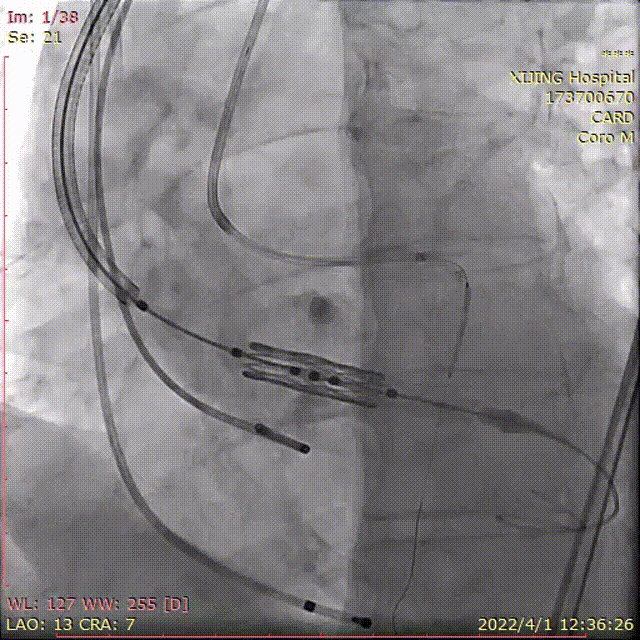

术中DSA影像:

术前造影并测压,显示AS+AR

左冠预埋球囊行冠脉保护

25mm球囊预扩张,有腰征,无漏

左右窦重合角度造影定位

右窦居中角度造影定位

多角度透视影像下显示可调弯输送器系统能保障瓣膜释放时与主动脉根部的同轴性。

释放26mmPrizValve,瓣架有腰征

术后造影微量PVL,瓣架形态位置理想

术后主动脉瓣上血压174/64(101),左心室血压187/22(77),最大跨瓣压差13mmHg。考虑球囊后扩张对左冠有影响,撤出左冠内球囊,手术结束。